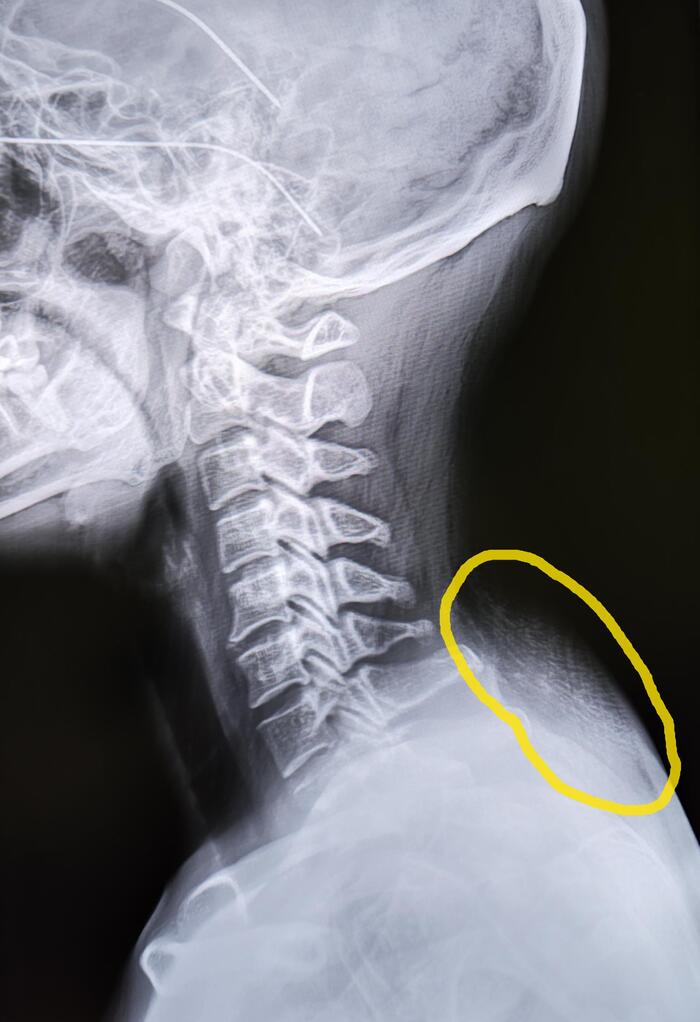

Пациентка (34года) пришла на Р-гр. ШОП, с жалобами на возникшее образование по задней поверхности шеи.

Вдовий горб – локальное скопление жировой ткани на границе шеи и спины при котором образуется характерная выпуклость.

Причины возникновения: недостаточная физическая активность, постоянное нахождение в позе, при которой голова согнута, эндокринные нарушения, мышечные дистрофии, менопауза(изменение гормонального фона).

У призывников данная патология практически не встречается, но в теории возможна, у молодых людей с избыточной массой тела, эндокринными нарушениями, в таком случае категория годности с диагнозом локальная липодистрофия(вдовий горб) будет присваиваться по ст.10 (Доброкачественные новообразования (кроме доброкачественных новообразований нервной системы и мозговых оболочек), новообразования in situ:)- в( наличие объективных данных без нарушения функции)-А2-годен к военной службе. Более "тяжелая" статья, в таком случае, будет выставляться терапевтом по поводу лишнего веса, эндокринных нарушений.